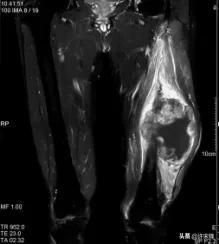

04 影像表现有何特点?

横纹肌肉瘤影像学表现缺乏特异性。

MRI检查时,T1WI表现为和软组织等信号或接近等信号,T2WI表现为高信号,如有坏死表现为更高信号区,如有出血,在T1WI、T2WI上均表现为高信号,增强后有强化表现。

男,65岁,左大腿横纹肌肉瘤,侵及左股骨